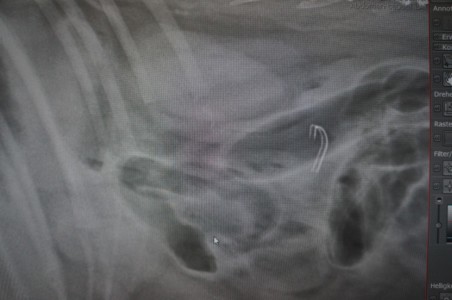

Digitales Röntgen

- allgemeine Aufnahmen

- Kontrastmittel-Aufnahmen

- Frakturbehandlung